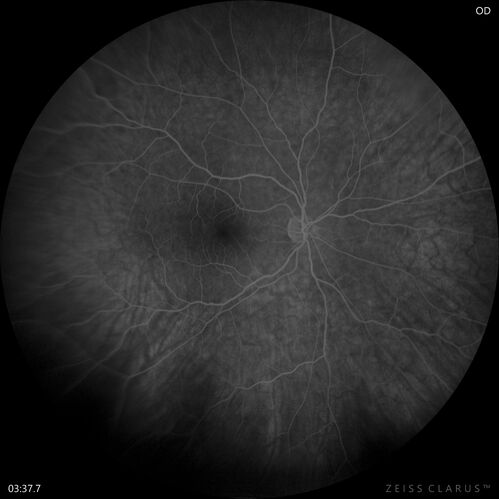

Retinal Angioma

46 year old female - Her original reason for an eye examination was that she had been in a car accident.  Then she saw that the vision was blurry in just the left eye.  Prior to that she had no known vision changes.  Since the accident she notices that her vision is better and her headaches are getting less bothersome.

PMhx benign, Meds: none

VA OD: Dcc20/20

VA OS: Dcc20/25